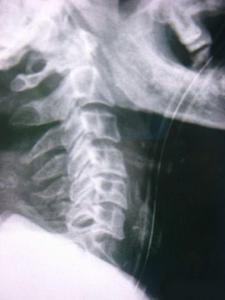

因為頸骨骨折也就是頸部脊椎骨的骨 折,在脊椎骨中央有神經(jīng)通過,這些神經(jīng)像電纜一樣能把大腦的命令傳達到全身,又能把身體的感覺傳向大腦。如果骨折切斷或壓迫脊椎骨中的神經(jīng),頸以下就會完 全麻痹,有時會使呼吸停止。

3、頸椎骨折常見于跳水誤跳入淺游泳池,或從很高的地方墜落以及交通事故等。

體位護理和體溫監(jiān)測 保持頭、頸、肩一致性活動,防止頸椎錯位。翻身時要一個人固定頭部,一個人搬動軀干,并注意顱骨牽引,防止滑脫,保持牽引繩與軀干在同一軸線上,床頭抬高15°~30°。顱骨牽引鋼針口處滴75%酒精4~5滴,每日更換敷料一次。由于脊髓損傷,植物神經(jīng)功能紊亂,全身交感神經(jīng)支被切斷,不能適應周圍環(huán)境溫度的變化而出現(xiàn)高熱,病人一旦出現(xiàn)高熱,體溫>38.5℃(腋下),即給予物理降溫,必要時給4℃冰生理鹽水300ml低壓灌腸,采取積極措施降溫。